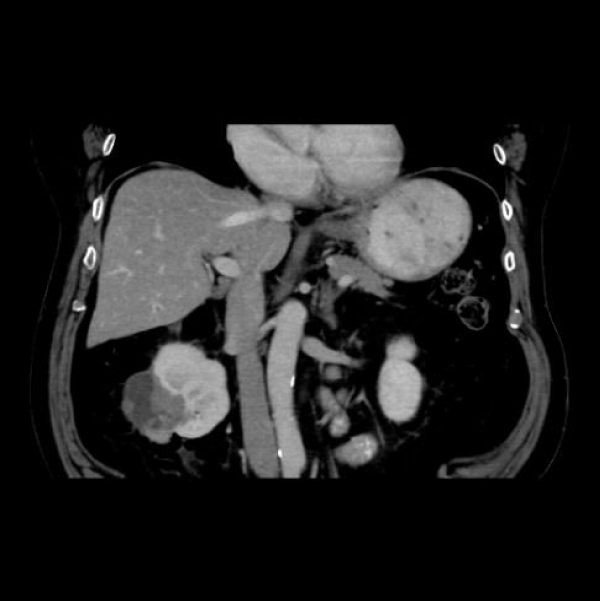

Renal cell carcinoma (RCC) is the ninth and fourteenth most common carcinoma in men and women respectively, alongside being the most lethal urological malignancy. RCC accounts for up to 90% of all kidney cancers, and up to 80% of all SRM. RCC constitutes Clear Cell (Figures 4-6), 75%, Papillary, around 15% to 20%, Chromophobe (Figures 7-9), 5% and other rarer subtypes. Clear Cell is the most common variant with the worst prognosis as it commonly presents at an advanced stage. Papillary type is more frequent in smaller lesion sizes [1,2,3,9-15].

Figure 5: Left renal Clear Cell RCC.

Download Image

Figure 6: Right renal Clear Cell RCC.